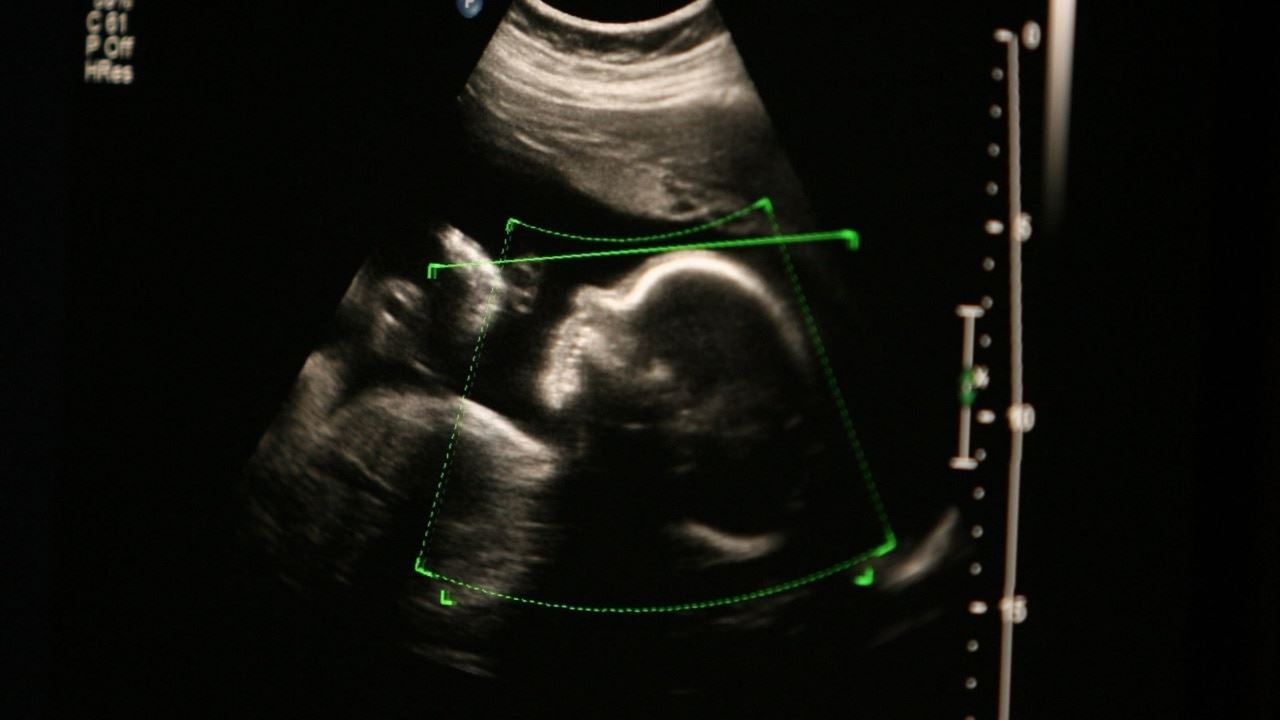

سقط جنین در استرالیای غربی دیگر جرم محسوب نمی‌شود

پارلمان استرالیای‌غربی جرم‌زدایی از سقط جنین را با اکثریت آراء مورد تصویب قرار داد. بدین ترتیب برخی از زنان این ایالت مجبور نخواهند بود برای انجام سقط جنین به سایر نقاط کشور سفر کنند.

به گزارش رادیونشاط، به بیانی دیگر پس از 25 سال قانون سقط جنین در استرالیای غربی مورد بازنگری قرار گرفته و با تصویب پارلمان، پایان بارداری و سقط جنین از قوانین کیفری این ایالت حذف شده و دیگر جرم محسوب نخواهد شد.

از سوی دیگر زنان متقاضی سقط جنین نیازی به اخذ گواهی و تاییدیه از دو پزشک نداشته و نظر یک پزشک برای قطع بارداری کفایت می‌کند.زمان مجاز برای اقدام به سقط جنین نیز از هفته بیستم به هفته بیست و سوم تغییر کرده است.

بدین ترتیب پایان بارداری برای مادران دارای جنین‌های مبتلا به ناهنجاری که معمولا تا هفته‌های هجدهم تا بیست و دوم نهفته باقی می‌مانند، آسانتر خواهد شد.

علاوه براین انجام مشاوره اجباری و کسب مجوز برای سقط جنین‌ در ماه‌های آخر بارداری نیز لغو شده است.

راجر کوک ،نخست وزیر استرالیای غربی، اظهار داشت، تغییرات جدید رفع موانع بالینی غیرضروری در سقط جنین را در پی خواهد داشت.

براساس مقررات جدید، عدم ارائه خدمات سقط جنین توسط پزشکان بنا به دلایل وجدانی مجاز است. اما این گروه از پزشکان می‌توانند بیماران خود را به مراکز مربوط ارجاع داده و در خصوص نحوه درمان به آن‌ها توضیح دهند.

علیرغم جرم‌زدایی از سقط جنین در استرالیای غربی، اما انجام این‌گونه عمل‌های جراحی توسط افراد فاقد صلاحیت کافی و غیرمجاز در این ایالت، همچنان جرم محسوب می‌شود..